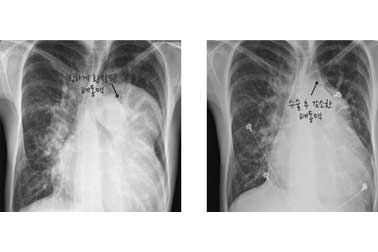

사례(2)

앱스타인 기형을 수술받지 않은채 살아온 54세 환자의 사진

수술 후(우측) 흉부X선 사진 비교수술 후 심장의 크기가 감소하고 있습니다.